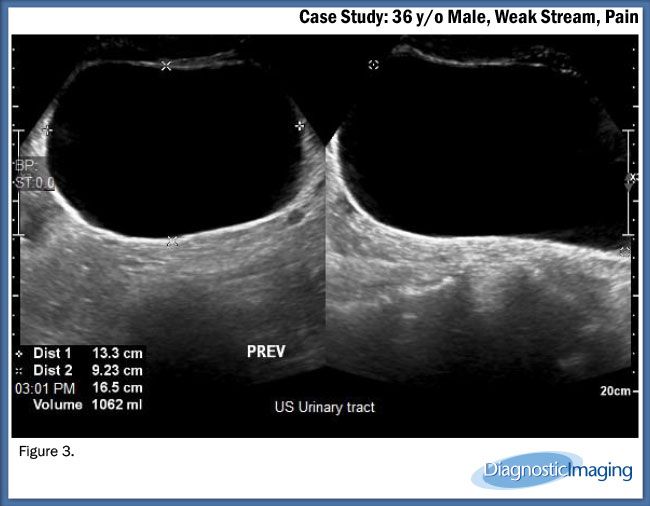

Case History: 36-year-old male presented with weak stream and pain.

Case History: A 36-year-old male presented with weak stream and pain.